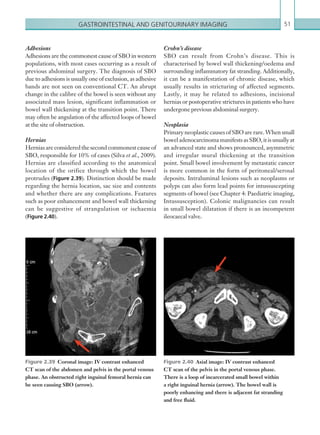

Adhesions51

Hernias51

Crohn’s disease51

Neoplasia51